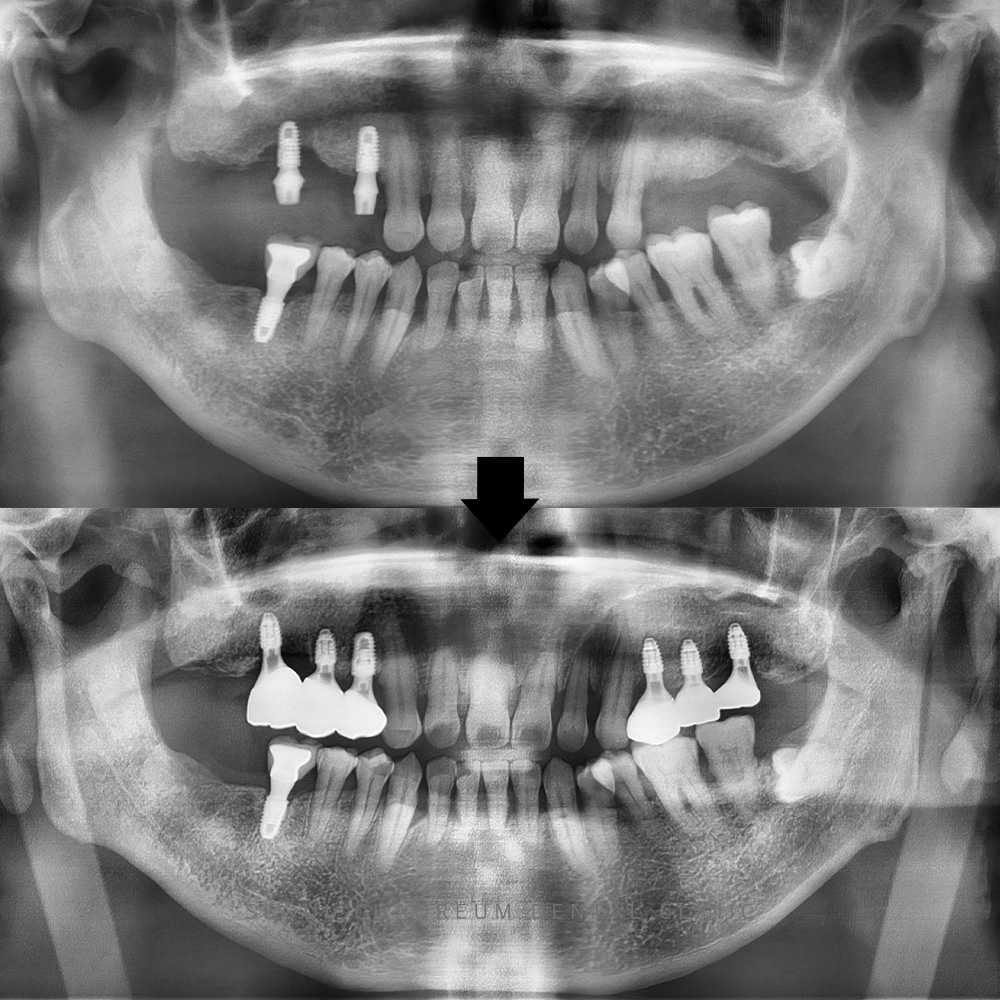

병점임플란트, 임플란트 받았던 곳이 문제가 생기고 위 앞니 보철 흔들려요 치아는 서로 균형을 이루며 기능하기 때문에, 특정 부위에 문제가 발생하면 인접 치아까지 영향을 받는 경우가 많습니다. 특히 어금니와…